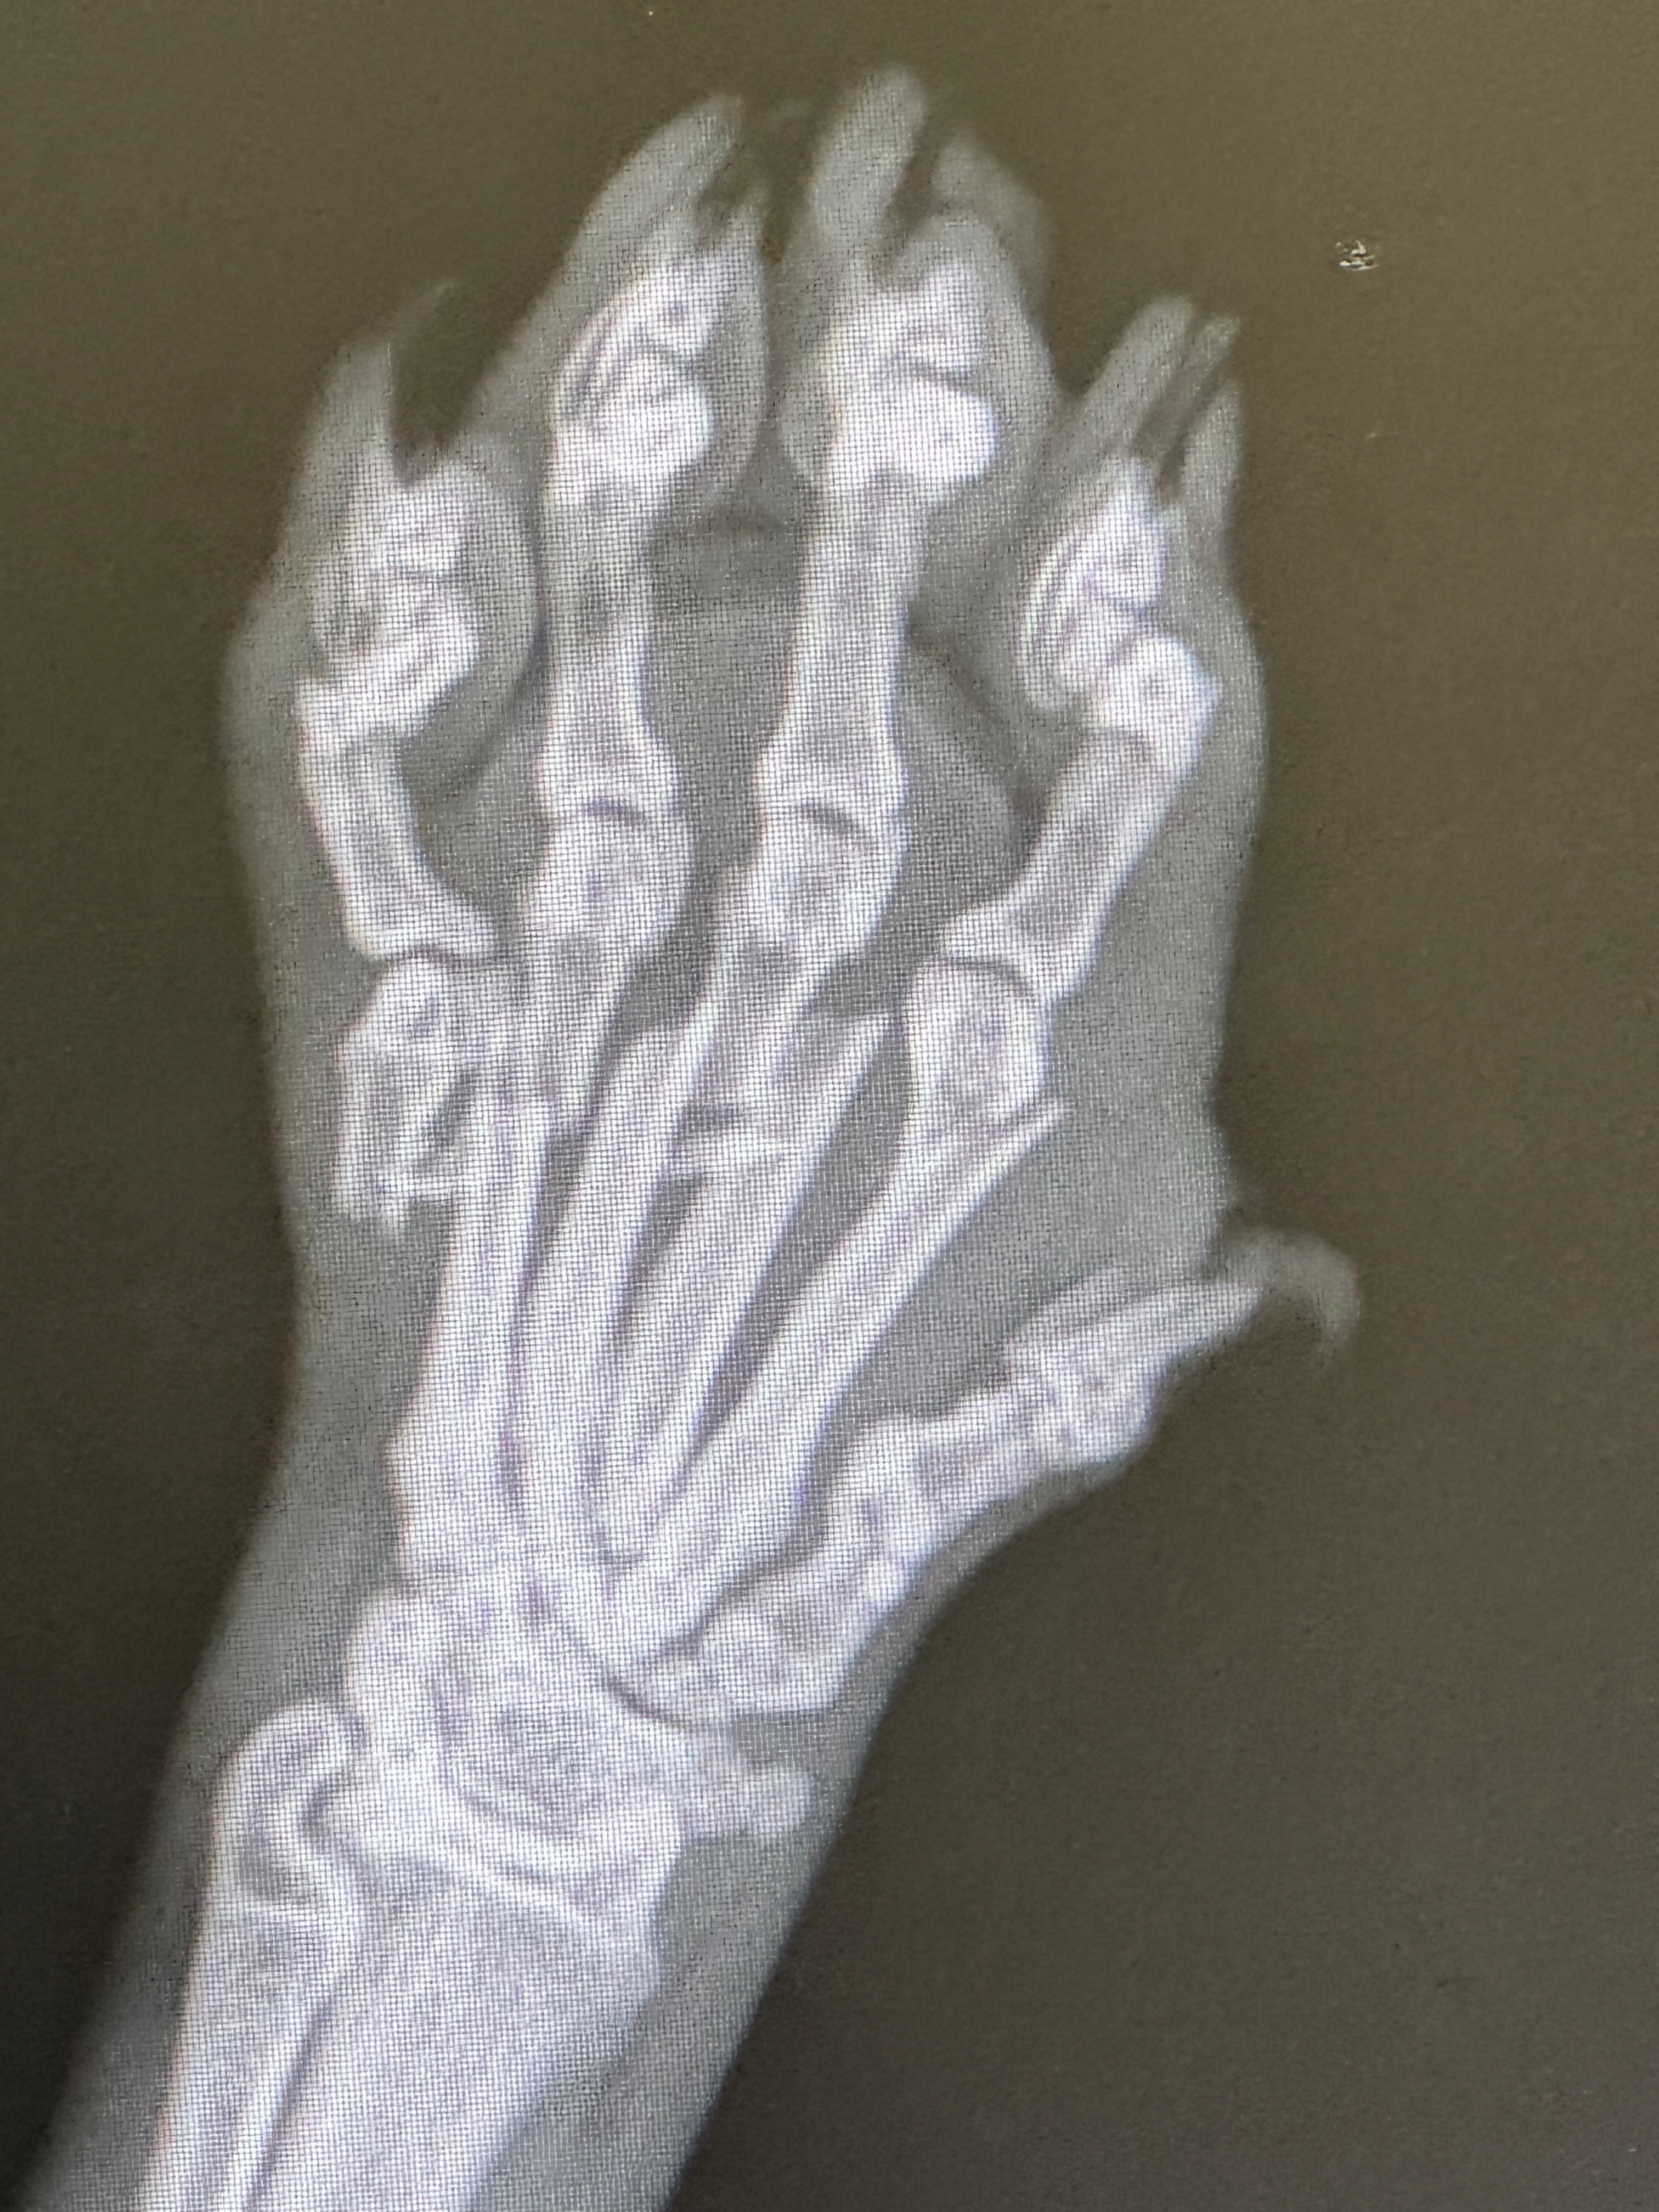

A few days ago, something awful happened. Loki accidentally smashed his paw under a falling table, breaking every one of the bones in his foot. My heart broke seeing him in so much pain. When I rushed him to the vet, they told me something I never expected to hear:

because of where the break happened — in his paw — the usual way to fix it isn’t possible. Cats can’t just have the paw repaired or partially amputated. Normally, the only option would be to remove the entire leg.

But Loki’s vet has been absolutely incredible — they truly put him first. After seeing the x-rays, the vet consulted with a specialist to see if there was any way to save his leg. Miraculously, the specialist said he can perform an emergency surgery to place pins in Loki’s toes and repair the bones.

That surgery would give Loki the chance to walk again on all four paws. Without it, the only option left would be a full amputation — but because Loki is a big boy, he wouldn’t adapt well to life on three legs. His vet made it clear: they’re trying to save his leg because they know how hard it would be for him to recover otherwise.